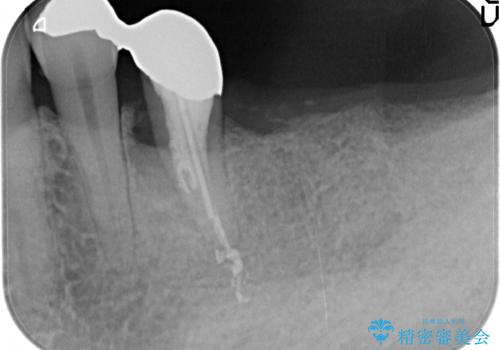

- 失ってしまった左下の奥歯にインプラント治療を受けたいと来院されました。

左下の欠損部には強度・表面性状に優れるストローマン社製インプラントを埋入し、合わせて噛み合う上顎の歯もクラウン再補綴による整備を行い安定した咬合関係の構築を目指します。

歯を失った期間が長くなると、対合する歯が伸びてくることによる補綴スペースの狭小化がしばしば見られます。

今回左下にインプラント治療を行うにあたり、対合する上顎の歯もいっしょに治療を行ったことで安定した咬合関係を構築することができました。